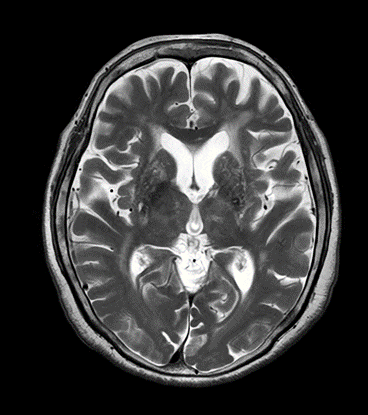

MRI検査

MRIは強力な磁場を利用し、コントラストの高い断層画像をさまざまな方向から画像化する検査です。